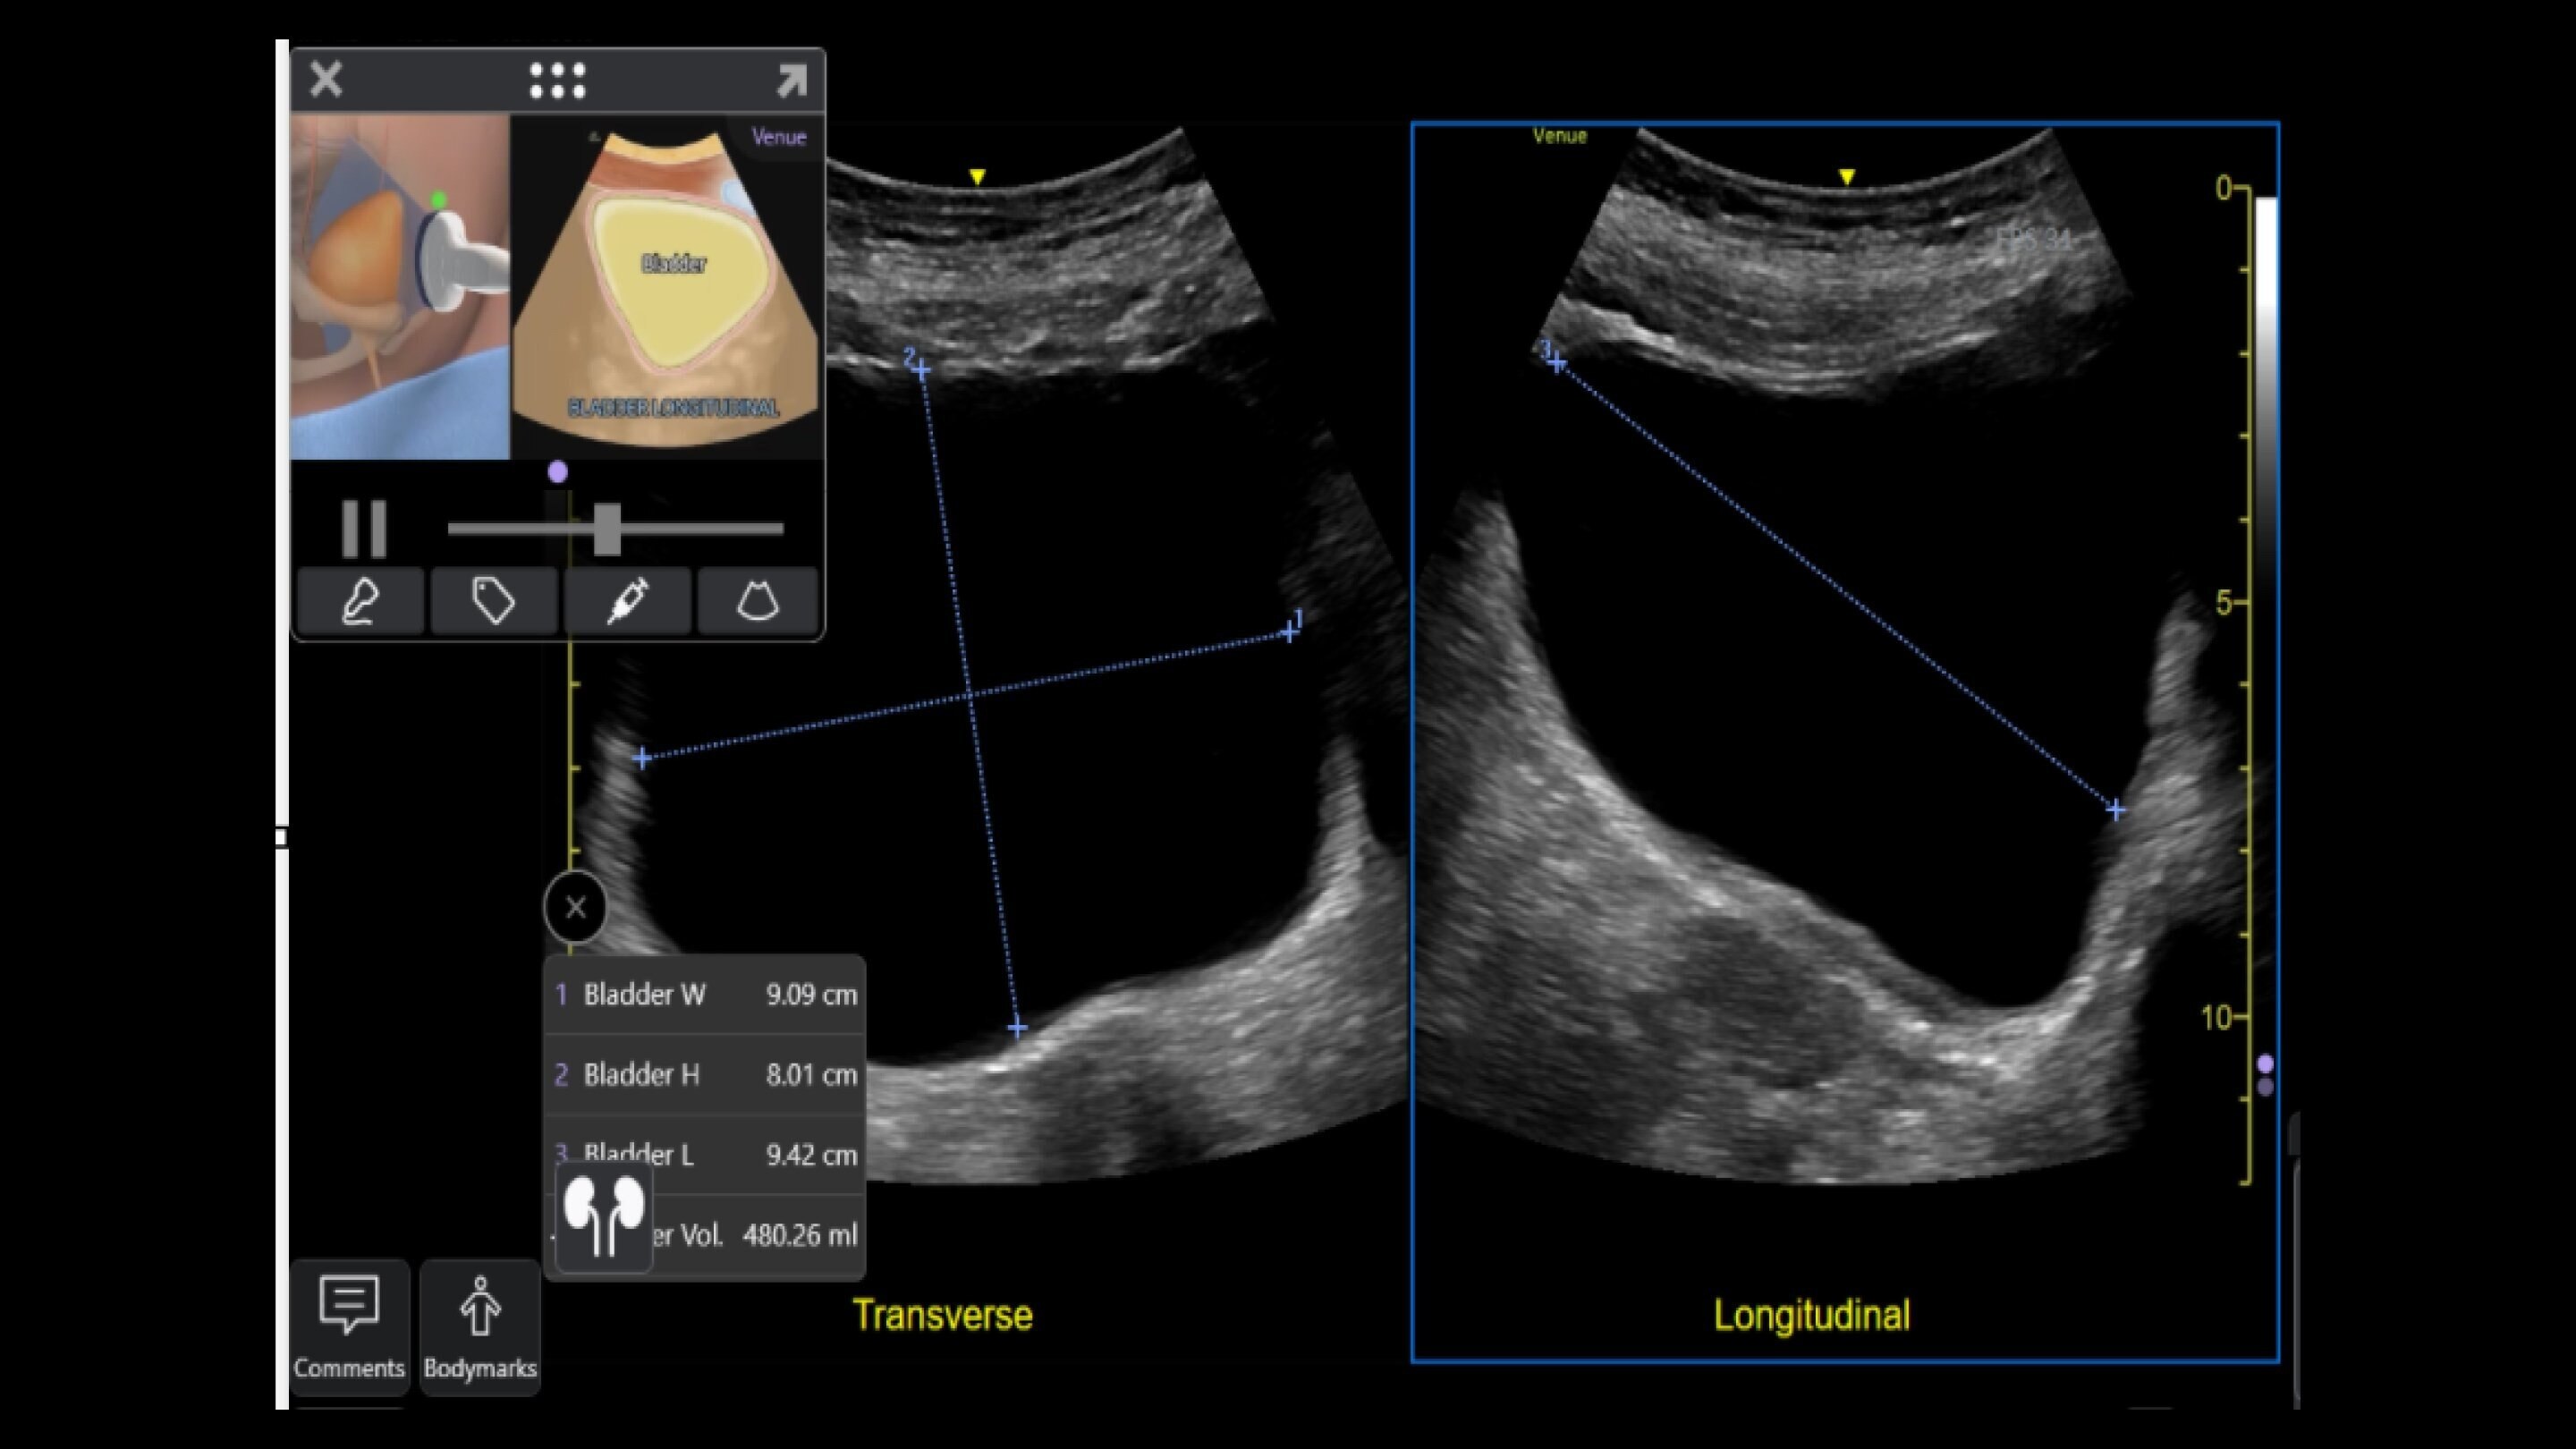

Emergency medicine

Enables assessments for a variety of anatomy all with a single device. Supports deep and shallow scanning with seamless data connectivity.